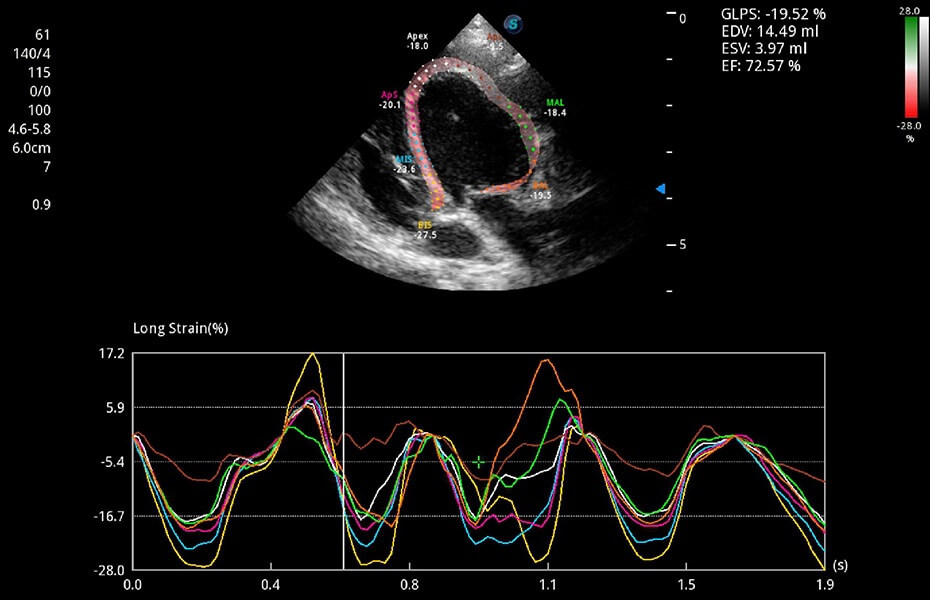

ProPet 60 作為一款高端臺(tái)式動(dòng)物超聲設(shè)備,為動(dòng)物醫(yī)生的日常診斷提供了一系列貼合動(dòng)物臨床需求、解決臨床實(shí)際問(wèn)題的高級(jí)成像功能。憑借全系列高清探頭,滿(mǎn)足醫(yī)生對(duì)腹部、心臟、生殖、淺表、肌骨等成像的所有需求,切實(shí)幫助您提升檢查效率,提高診斷信心。